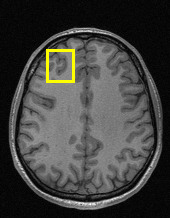

Edge preserving has always been a crucial concern in the design of reconstruction models. To improve the quality of reconstructed images and preserve image edges, some works suggested introducing edge priors in the original restoration problem to preserve image edges [4, 34]. However, they will suffer from complicated algorithm design and time-consuming training processes. Recently, some more efficient methods have been proposed to use edge maps as external guidance for image restoration. For example, Yang et al. [48] used off-the-shelf edge detectors to extract image edges from the degraded images. Fang et al. [12] predicted image edges by constructing an edge reconstruction network. Huang et al. [18] designed a novel dual discriminator GAN framework for solving fast multi-channel MRI, in which one GAN network is built for edge information enhancement. Inspired by these methods, we also consider introducing image edge prior as external guidance to MRI reconstruction since 1) image edges are prominent and distinguishable features in MRI (see Fig. 1), which can serve as a good guide to the model to recover high-frequency details; 2) the ground truth edges can be easily fetched via ordinary edge extraction operators, like Canny, Sobel, and Prewitt, which means that the edge maps can be learned in a data-driven manner. However, how to effectively utilize image edge priors to guide image reconstruction still remains a challenge. In some methods, edge information was simply concatenated with the input image and passed to the next stages. Though this is a simple way to utilize the edge priors, it may not give full play to the guiding role of the edge priors. Therefore, in this work, we want to explore a more efficient and effective mechanism to fully take advantage of image edge priors.

(a)

(b)

(c)

fastMRI is a large-scale MR dataset jointly established by Facebook AI Research and NYU Langone Health. It provides both knee and brain datasets for evaluation. In our work, we use the multi-coil knee dataset, which was acquired on three clinical 3T systems or one clinical 1.5T system using a 15-channel knee coil array. The dataset includes data from two pulse sequences, yielding coronal proton-density weighting with (PDFS) and without (PD) fat suppression. As is shown in Fig. 1, PD images usually contain more structural and prominent edge features than PDFS images, which suggests that it is more challenging to use edge guidance on PDFS datasets. Therefore, we explore the effectiveness of EAMRI on these two modalities. Following [13], for both PD and PDFS knee datasets, we separately filter out 227 volumes (8332 slices) for training and 24 volumes (1665 slices) for testing. The dataset is centrally cropped to .

Moreover, in Fig. 6, we provide a visual comparison of the reconstruction results of these models. We can see that EAMRI has fewer bright spots in the heatmaps, which means less error between the EAMRI reconstructed image and the ground truth image. Meanwhile, according to the zoomed-in images of the selected areas, we can observe that our EAMRI can reconstruct more clean and accurate edges. This further validates the validity of EAMRI. Both the quantitative and the qualitative results for the single-coil MRI reconstruction demonstrate the effectiveness of EAMRI.